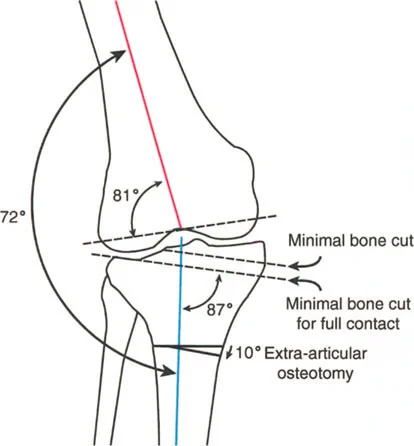

- جراحات قطع العظم وتقويم المحاور

لطالما كان التركيز الأساسي في جراحة العظام، خاصة لطلبة الجراحة، ينصب على التشوهات الثابتة للأطراف السفلية. هذه التشوهات تشمل انحرافات العظام الثابتة، والتئام العظام بشكل خاطئ، وعدم التئامها، وتيبس المفاصل، وهي حالات يسهل قياسها وتحديدها عبر الأشعة السينية الثابتة. ولكن، لكي يتقن الجراح حقًا إعادة بناء الأطراف السفلية، وتخطيط عمليات قطع العظم (Osteotomy)، وجراحات استبدال المفاصل المعقدة، يجب عليه أن يتجاوز هذا الفهم التقليدي ويتعمق في العالم الحركي والسائل للتشوهات الديناميكية.

التشوهات الديناميكية هي اختلالات وظيفية تتأثر بموقع المفصل في الفراغ، ووظيفة العضلات، والأهم من ذلك، الطول الفعلي والتوجيه المكاني لأذرع الرافعة الهيكلية أثناء الحركة. على عكس التشوهات الثابتة التي تكون موجودة بغض النظر عن الحركة، فإن التشوهات الديناميكية تظهر بوضوح أو تتفاقم عندما يحاول المريض أداء حركة معينة، مثل المشي أو الوقوف.

في حين أن التشوهات الديناميكية تُناقش غالبًا في سياق أمراض الأعصاب والعضلات لدى الأطفال، فإن المبادئ البيوميكانيكية التي تحكمها تنطبق عالميًا على إعادة بناء العظام لدى البالغين. يشمل ذلك سيناريوهات إعادة البناء المعقدة للغاية، مثل استبدال مفصل الركبة الكلي (TKR) واستبدال مفصل الورك الكلي (THR) المرتبطة بالانحرافات الشديدة خارج المفصل. إن فهم الأذرع الرافعة هو المتطلب الأساسي لإتقان هذه التقنيات المتقدمة في جراحة المفاصل وقطع العظم، وهو ما يتقنه الأستاذ الدكتور محمد هطيف في ممارسته اليومية.

بشكل خاص، يصف خلل وظيفة الذراع الرافعة حالة سريرية تتشوه فيها أذرع الرافعة الداخلية و/أو الخارجية بسبب سوء محاذاة العظام، أو التشوهات الالتوائية، أو تيبسات المفاصل الموضعية.